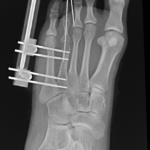

The surgeon in preparation for each surgery preconstructs a customized apparatus. Using wires or pins, the apparatus is surgically attached to the affected limb. Surgery is usually performed percutaneously through small incisions. Special care is taken to minimize injury to the bone and surrounding soft tissue, nerves and blood vessels when making specialized bone cuts.

The actual lengthening or straightening of the limb begins 1-2 weeks after surgery. At that time, adjustments are made to the apparatus usually four times a day. Detailed instructions are provided to the patient to ensure they fully understand what is required.

During the adjustment phase the patient is followed up in the rooms every two weeks with clinical examination and x-rays. A close scrutiny is maintained to identify any complications early.